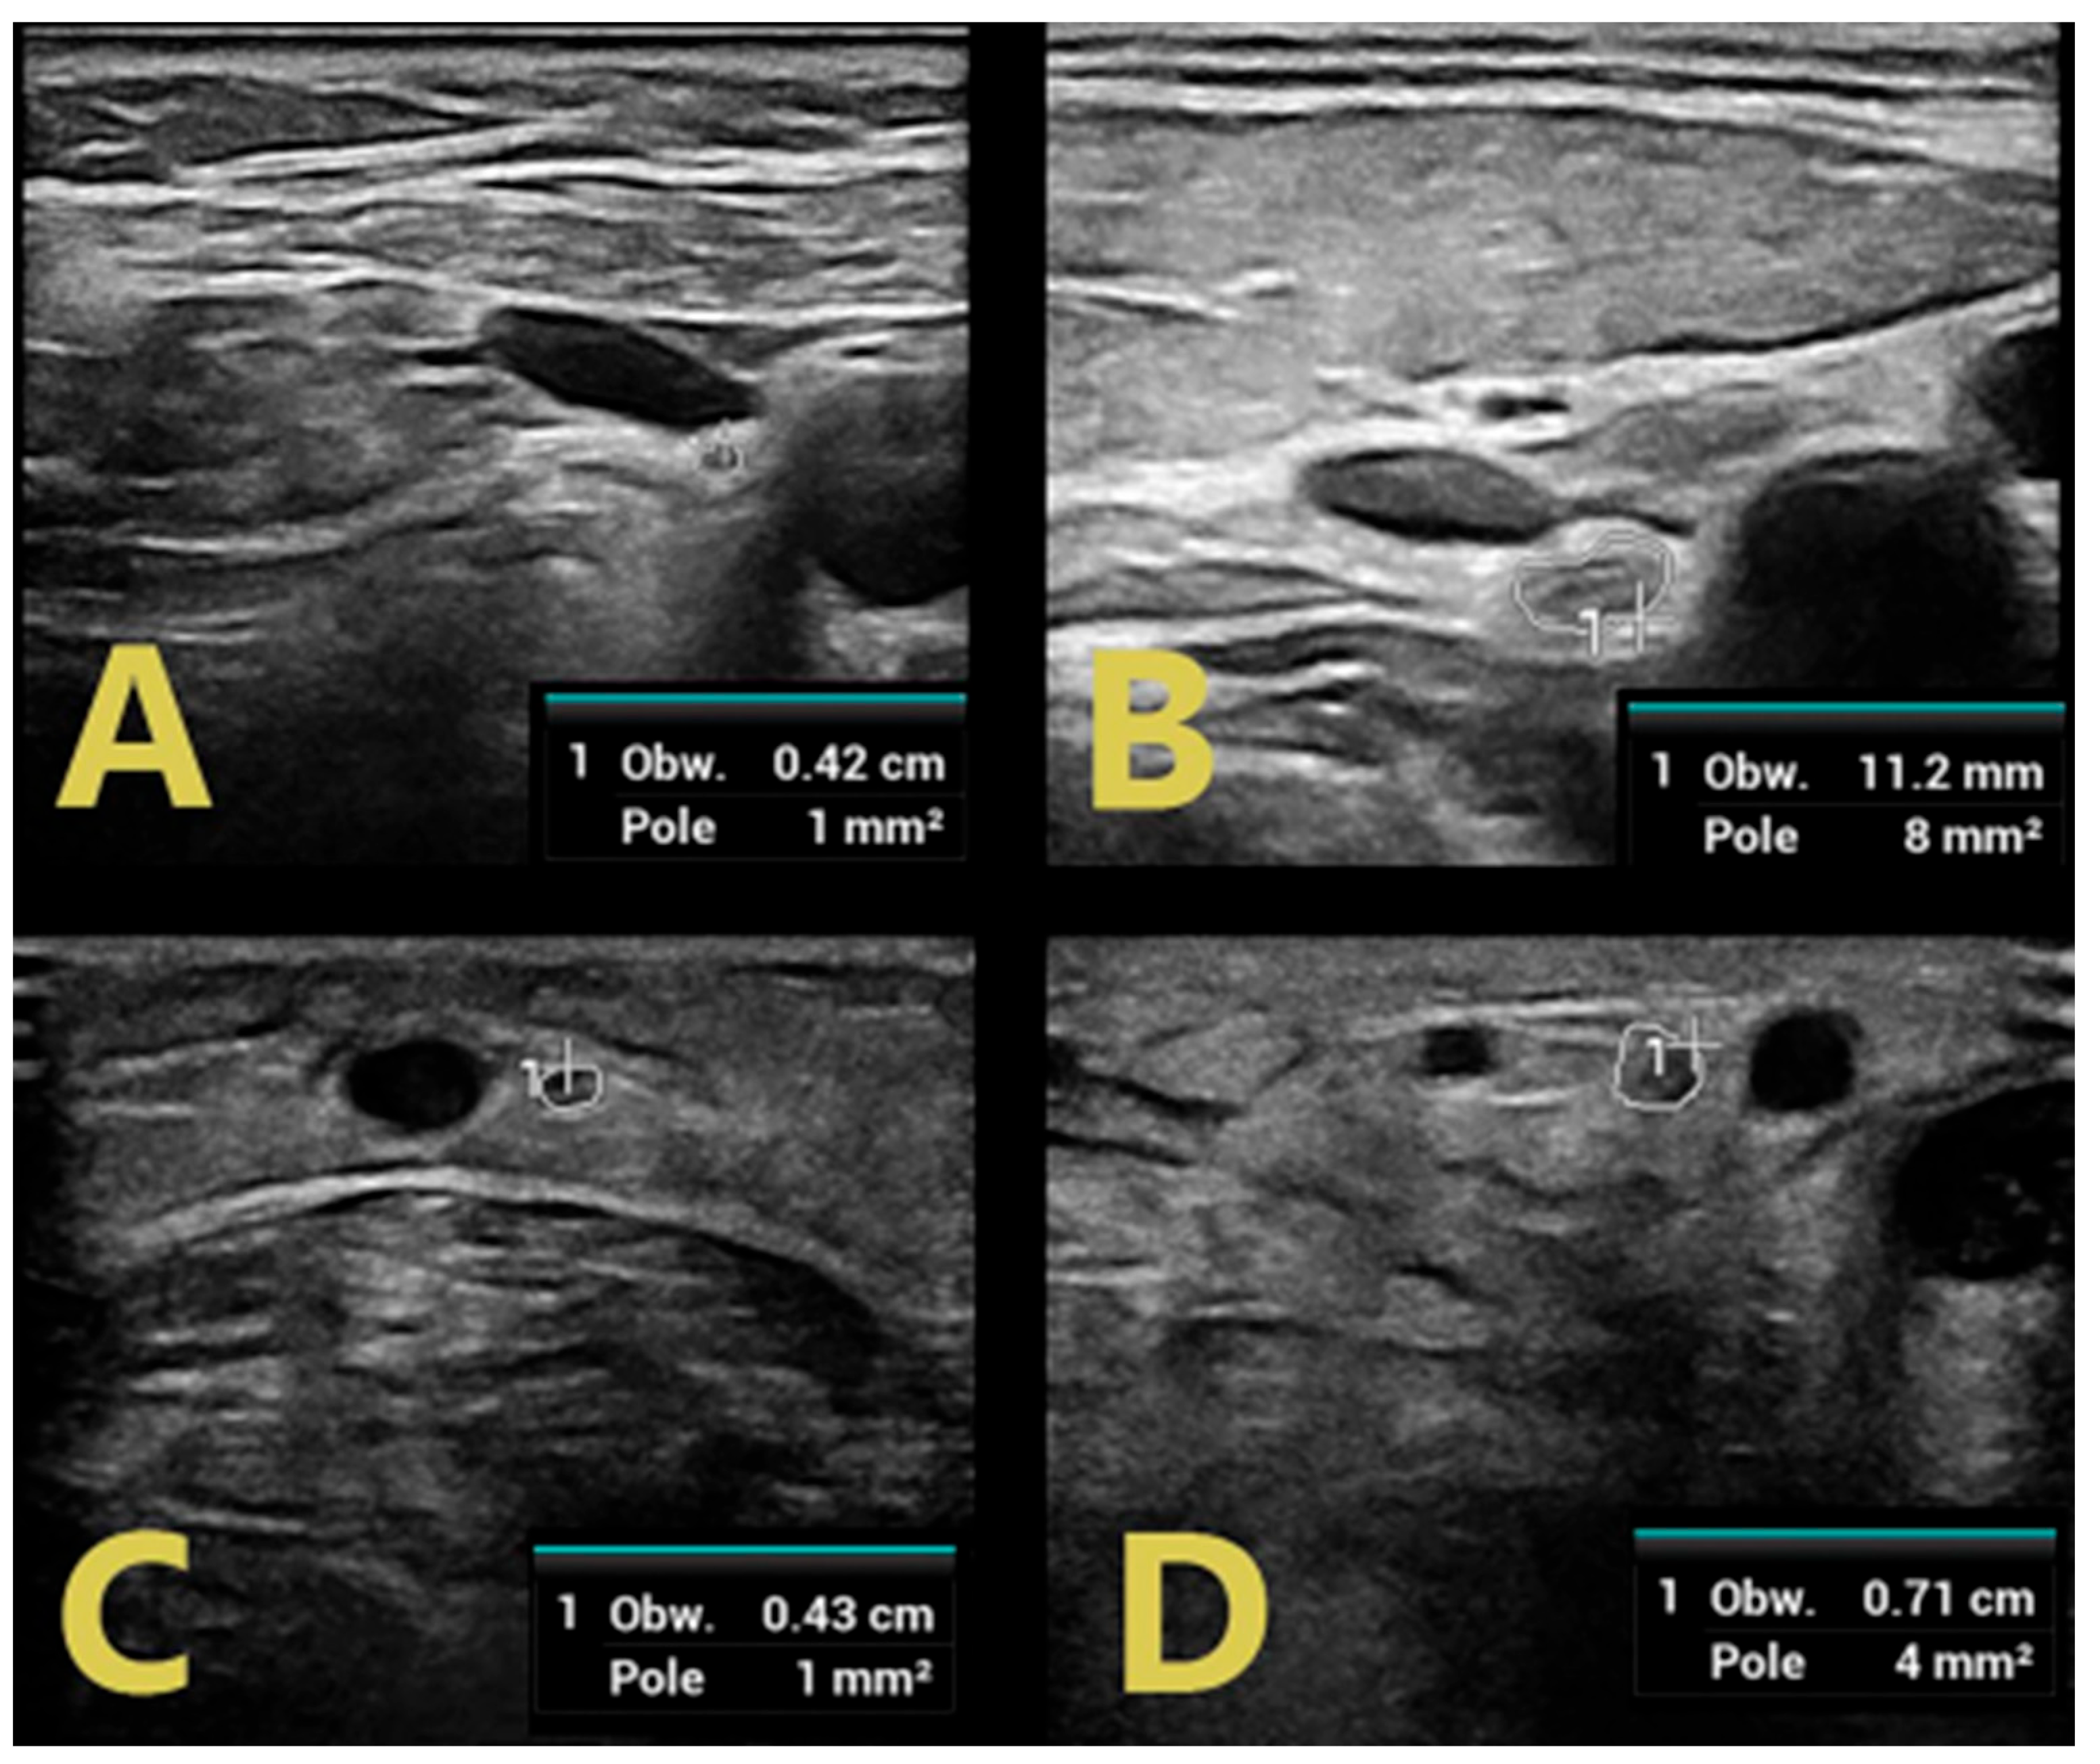

| SM | >6 months | - | 3/5 (ataxia) | ↑ CSA RMN, RUN, SBRRN ↑ C5 LAX CSA ↑↑ C6 | ↑↑ CSA RTN, RPN, ↑ CSA RSN | ↑ duration LMR | ↑ duration RMP |

| LAX CSA ↑ CSA VN | |||||||

| DJ | 17 months | - | 3/5 | ↑↑ CSA LMN ↑ CSA LUN ↑ C5 LAX CSA ↑↑ C6 LAX CSA ↑ CSA VN | ↑↑ CSA LTN, LPN, ↑ CSA LSN | ↑ duration LMM | ↑F latency LMT |

| DR | 6 months | - | 3/5 | ↑↑ CSA RMN ↑ CSA RUN ↑ C5 LAX CSA ↑↑ C6 LAX CSA ↑ CSA VN | ↑ CSA RTN, RPN, RSN | ↑ F latency RMT, LMT | |

| SZ | >5 months | - | 2/5 | ↑ CSA RMN, RUN ↑ C5 LAX CSA ↑↑ C6 LAX CSA ↑ CSA VN | ↑↑ CSA RTN, RPN, RSN | F wave absence RMT, LMP | |

| WJ | 17 months | - | 3/5 | ↑↑ CSA RMN ↑ C5 LAX CSA ↑↑ C6 LAX CSA ↑ CSA VN | ↑↑ CSA RTN, RPN, RSN | ↑ duration RMP, RMT | |

| BA | 6 months | 4/5 | 3/5 | ↑↑ CSA RMN, RUN ↑ C5 LAX CSA ↑↑ C6 LAX CSA ↑ CSA VN | ↑↑ CSA RTN, RPN, RSN | ↑ duration RMU | ↑ duration RMT |

| BD | 14 days | - | 2/5 | ↑ C5 LAX CSA ↑ C6 LAX CSA | ↑ CSA LTN, LPN | ↑ duration RMU, LMP | F-wave absence RMP |

| SMi | 4 days | 4/5 | 2/5 | ↑↑ CSA RMN ↑ C5 LAX CSA ↑ C6 LAX CSA | ↑ CSA RTN, | ↑ duration RMU | ↑F latency RMP, LMP ↑ duration RMP, LMP, RMT |

| LW | 6 weeks | - | 3/5 | ↑↑ CSA RMN, ↑ RUN ↑ C5 LAX CSA ↑ C6 LAX CSA | ↑ CSA RTN, RPN | ||